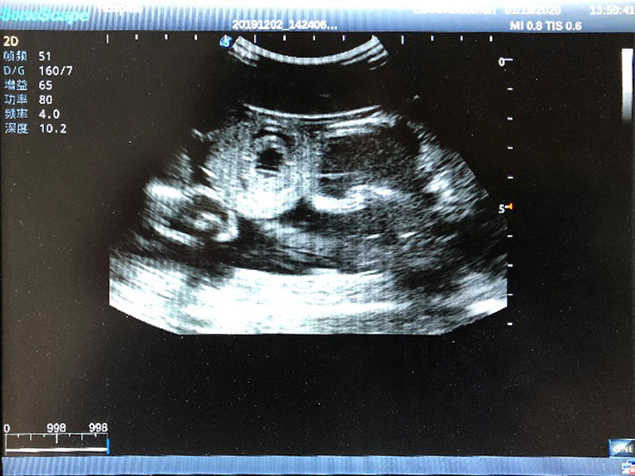

2)  High quality ultrasound image with clear structures like gallbladder, liver, intestines, arteries and veins etc.

3)  Compatible with all types of clinical ultrasound machines

4)  ltrasound gallbladder pathologies like cholecystitis, gallstone and polypoid degeneration

5)  Normal & pathological ultrasound live and intestine models inside